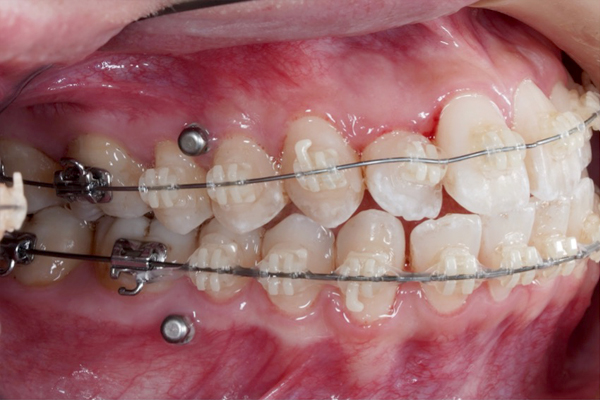

|20代女性・

ワイヤー矯正・3ヵ月経過の途中症例

【3ヶ月経過の変化】

• 前歯の重なりが減り、アーチが広がってきました。

• 下の歯はほとんど並びました。

• インプラントアンカーにより歯を後ろに動かします。